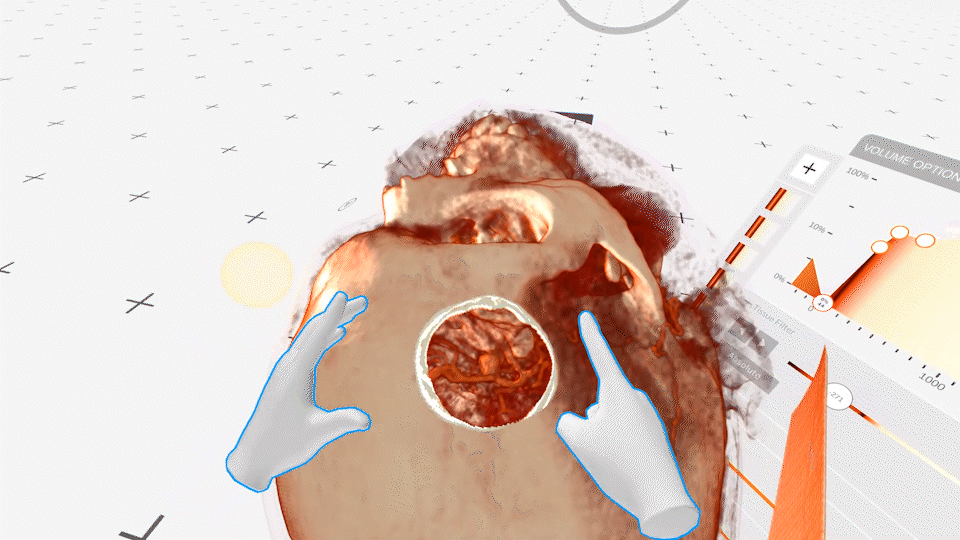

A groundbreaking approach to tackling complex lacrimal obstructions.

Read more User story

Endoscopic dacryocystorhinostomy in posttraumatic nasolacrimal duct obstruction.